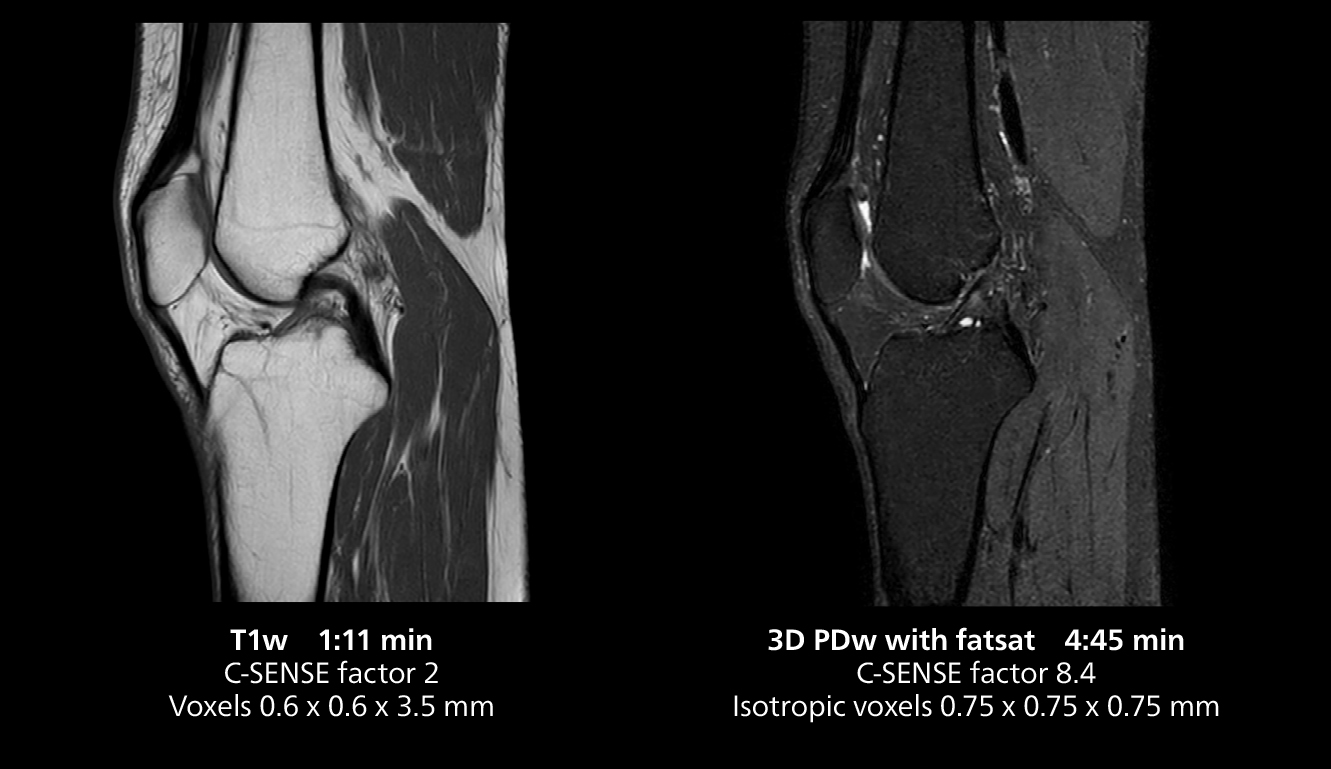

The isotropic high resolution 3D sequence in this MRI case allows for reformatting to obtain other orientations with high quality. Acquired on the MR 5300 system.

“We have more speed in 3D sequences,” Dr. Gellée states. “With Compressed SENSE, we can replace two or three 2D scans withone high-quality 3D scan. High quality additional orientations are then obtained by post-processing of the 3D data set, thus saving scanning time.”